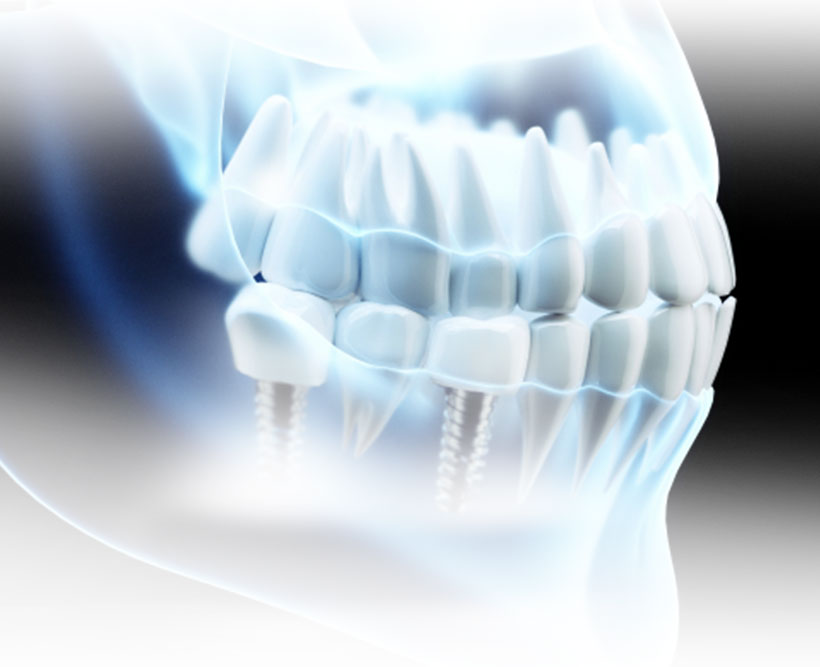

インプラント

歯が抜けてしまった方に

インプラントは歯のアンチエイジングです

失った歯を最も機能的に、洗練された方法で修復するのがインプラントです。

失ってしまった歯の根が本来あった場所に人工的な金属の土台をうめこみ、その上に人工的な歯を固定させる方法です。

歯根が失われたままの状態で治療を行うブリッジや入れ歯とは異なり、失った歯が1本だけの場合、歯のない部分が広い場合や数本失ってしまった場合、または歯がまったくない場合でも、様々なケースでのインプラント治療が可能です。